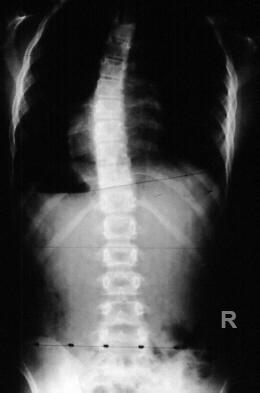

summary Adolescent Idiopathic Scoliosis is a coronal plane spinal deformity which most commonly presents in adolescent girls from ages 10 to 18. Diagnosis is made with full-length standing PA and lateral spine radiographs. Treatment can be observation, bracing, or surgical management depending on the skeletal maturity of the patient, magnitude of deformity, and curve progression. Epidemiology Incidence most common type of scoliosis incidence of 3% for curves between 10 to 20° incidence of 0.3% for curves > 30° Demographics most commonly presents in children 10 to 18 yrs 10:1 female to male ratio for curves > 30° 1:1 male to female ratio for small curves right thoracic curve most common left thoracic curves are rare and indicate an MRI to rule out cyst or syrinx Etiology Pathophysiology unknown potential causes multifactorial hormonal (melatonin) brain stem proprioception disorder platelet calmodulin abnormal development of neurocentral synchodrosis (NCS) cartilaginous plate that forms between the centrum and posterior neural arches closure occurs in characteristic order cervical NCS by 5-6 years old lumbar NCS by 11-12 years old thoracic NCS by 14-17 years old most have a positive family history Curve Progression risk factors for progression (at presentation) curve magnitude before skeletal maturity > 25° before skeletal maturity will continue to progress after skeletal maturity > 50° thoracic curve will progress 1-2° / year > 40° lumbar curve will progress 1-2° / year remaining skeletal growth younger age < 12 years at presentation Tanner stage (< 3 for females) Risser Stage (0-1) Risser 0 covers the first 2/3rd of the pubertal growth spurt correlates with the greatest velocity of skeletal linear growth open triradiate cartilage peak growth velocity is the best predictor of curve progression in females it occurs just before menarche and before Risser 1 (girls usually reach skeletal maturity 1.5 yrs after menarche) most closely correlates with the Tanner-Whitehouse III RUS method of skeletal maturity determination if curve is >30° before peak height velocity there is a strong likelihood of the need for surgery curve type thoracic more likely to progress than lumber double curves more likely to progress than single curves Classification King-Moe Classification five part classification to describe thoracic curve patterns and help guide surgeons implanting Harrington instrumentation link to King-Moe classification (not testable) Lenke Classification more comprehensive classification based on PA, lateral, and supine bending films helps to decide upon which curves need to be included within the fusion construct link to Lenke classification (not testable) Presentation School screening patients often referred from school screening where a 7° curve on scoliometer during Adams forward bending test is considered abnormal 7° correlates with 20° coronal plane curve Physical exam special tests Adams forward bending test axial plane deformity indicates structural curve forward bending sitting test can eliminate leg length inequality as cause of scoliosis other important findings on physical exam leg length inequality midline skin defects (hairy patches, dimples, nevi) signs of spinal dysraphism shoulder height differences truncal shift rib rotational deformity (rib prominence) waist asymmetry and pelvic tilt cafe-au-lait spots (neurofibromatosis) foot deformities (cavovarus) can suggest neural axis abnormalities and warrant a MRI asymmetric abdominal reflexes perform MRI to rule out syringomyelia Imaging Radiographs recommended views standing PA and lateral Cobb angle > 10° defined as scoliosis generated by drawing lines parallel to the vertebrae that are most tilted towards each other and then the angle created by those lines intra-interobserver error of 3-5° spinal balance coronal balance is determined by alignment of C7 plumb line to central sacral vertical line sagittal balance is based on C7 plumb from center of C7 to the posterior-superior corner of S1 stable zone between lines drawn vertically from lumbosacral facet joints stable vertebrae most proximal vertebrae that is most closely bisected by central sacral vertical line neutral vertebrae rotationally neutral (spinous process equal distance to pedicles on PA xray) end vertebrae end vertebra is defined as the vertebra that is most tilted from the horizontal apical vertebra apical vertebrae the apical vertebraeis the disk or vertebra deviated farthest from the center of the vertebral column clavicle angle best predictor of postoperative shoulder balance MRI should extend from posterior fossa to conus purpose is to rule out intraspinal anomalies indications to obtain MRI atypical curve pattern (left thoracic curve, short angular curve, apical kyphosis) rapid progression excessive kyphosis structural abnormalities neurologic symptoms or pain foot deformities asymmetric abdominal reflexes a syrinx is associated with abnormal abdominal reflexes and a curve without significant rotation Treatment Based on skeletal maturity of patient, magnitude of deformity, and curve progression Nonoperative observation alone indications cobb angle < 25° technique obtain serial radiographs to monitor for progression bracing indication cobb angle from 25° to 45° only effective for flexible deformity in skeletally immature patient (Risser 0, 1, 2) goal is to stop progression, not to correct deformity outcomes 50% reduction in need for surgery with compliant brace wear of at least 13 hours a day poor prognosis with brace treatment associated with poor in-brace correction hypokyphosis (relative contraindication) male obese noncompliant (effectiveness is dose-related) the number needed to treat (NNT) is four in highly compliant patients Sanders staging system predicts the risk of curve progression despite bracing to >50 degrees in Lenke type I and III curves uses anteroposterior hand radiograph and curve magnitude to assess risk of progression despite bracing Operative treatment posterior spinal fusion indications cobb angle > 45° can be used for all types of idiopathic scoliosis remains gold standard for thoracic and double major curves (most cases) anterior spinal fusion indications best for thoracolumbar and lumbar cases with a normal sagittal profile anterior / posterior spinal fusion indications larges curves (> 75°) or stiff curves young age (Risser grade 0, girls <10 yrs, boys < 13 yrs) in order to prevent crankshaft phenomenon Techniques Bracing recommended for 16-23 hours/day until skeletal maturity or surgical intervention deemed necessary (actual wear minimum 12 hours required to slow progression) brace types curves with apex above T7 Milwaukee brace (cervicothoracolumbosacral orthosis) extends to neck for apex above T7 apex at T7 or below TLSO Boston-style brace (under arm) Charleston Bending brace is a curved night brace bracing success is defined as <5° curve progression bracing failure is defined 6° or more curve progression at orthotic discontinuation (skeletal maturity) absolute progression to >45° either before or at skeletal maturity, or discontinuation in favor of surgery skeletal maturity is defined as Risser 4 <1cm change in height over 2 visits 6 months apart 2 years postmenarchal Posterior spinal fusion fusion levels goals fusion should include enough levels to adequately maintain sagittal and coronal balance while being as minimal as safely possible to preserve motion typical fusion from proximal end vertebra to one or two levels cephalad to the stable vertebra double and triple major curves fuse to the distal end vertebra Harrington technique recommends one level above and two levels below the end vertebrae if these levels fall wilthin the stable zone Moe technique recommends fusion to the neutral vertebrae Lenke technique recommends including all major curves in the fusion and minor curves that are not flexible or are kyphotic extending fusion caudad to the touched vertebrae improves patient outcomes and radiographic correction touched vertebrae (TV) is the last cephalad vertebrae touched by the central sacral vertical line L5 level Cochran found increase incidence of low back pain with fusion to L5, and to a lesser extent L4. therefore, whenever possible, avoid fusion to L4 and L5 pelvis it is almost never required to fuse to the pelvis in idiopathic scoliosis pedicle screw fixation screw insertional torque correlates with resistance to screw pullout resistance to screw pullout increases by undertapping by 1mm curve correction segmental pedicle screw fixation allows increased coronal plane correction while lessening the need for anterior releases ASF with instrumentation advantage better correction while saving lumbar fusion levels disadvantage increased risk of pseudarthrosis when thoracic hyperkyphosis is present fusion levels typically fuse from end vertebra to end vertebra Neurologic Monitoring monitoring with somatosensory-evoked potentials (SSEPs) and/or motor-evoked potentials (MEPs) is now the standard of care motor-evoked potentials can provide an intraoperative warning of impending spinal cord dysfunction neurologic event defined as drop in amplitude of > 50% if neurologic injury occurs intraoperatively consider check for technical problems check blood pressure and elevate if low check hemoglobin and transfuse as necessary lessen/reverse correction administer Stagnaras wake up test remove instrumentation if the spine is stable Complications Neurologic injury paraplegia is 1:1000 increased risk with kyphosis, excessive correction, and sublaminar wires Pseudoarthrosis (1-2%) presents as late pain, deformity progression, and hardware failure an asymptomatic pseudarthrosis with no pain and no loss of correction should be observed Infection (1-2%) presents as late pain incision often looks clean Propionibacterium acnes most common organism for delayed infection (requires 2 weeks for culture incubation) attempt I&D with maintenance of hardware if not loose and within 6 months Flat back syndrome early fatigability and back pain due to loss of lumbar lordosis rare now that segmental instrumentation addresses sagittal plane deformities decreased incidence with rod contouring in the sagittal plane and compression/distraction techniques treat with revision surgery utilizing posterior closing wedge osteotomies anterior releases prior to osteotomies aid in maintenance of correction Crankshaft phenomenon rotational deformity of the spine created by continued anterior spinal growth in the setting of a posterior spinal fusion can occur in very young patients when PSF is performed alone and the anterior column is allowed continued growth avoided by performing anterior diskectomy and fusion with posterior fusion in very young patients SMA syndrome (superior mesenteric artery [SMA] syndrome) compression of 3rd part of duodenum due to narrowing of the space between SMA and aorta SMA arises from anterior aspect of aorta at level of L1 vertebrae presents with symptoms of bowel obstruction in first postoperative week associated with electrolyte abnormalities nausea, bilious vomiting, weight loss risk factors height percentile <50%; weight percentile < 25% sagittal kyphosis treat with NG tube and IV fluids Hardware failure late rod breakage can signify a pseudarthrosis Emergency department visits most often for minor medical complaints associated with older age at the time of surgery and more fusion levels Postoperative pain adjunctive short-term steroids have been shown to decrease opioid use Prognosis Natural history increased incidence of acute and chronic pain in adults if left untreated curves > 90° are associated with cardiopulmonary dysfunction, early death, pain, and decreased self image